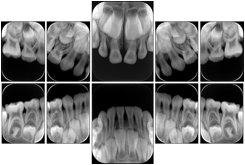

3. A patient in rural Minnesota experiences sudden vision loss and goes to a general ophthalmologist, who acquires OCT images and forwards them electronically along with a Structured Display to a retina specialist six travel hours away. The retina specialist is able to view the images in the standard layout that he is comfortable with, and to confirm that the patient has a choroidal neovascular membrane. He determines that is would be worthwhile for the patient to travel for treatment.

OCT Retinal Study with Cross Section and Navigation Structured Display

Figure OO-4. OCT Retinal Study with Cross Section and Navigation Structured Display

OO.1.3 Cardiology

Cardiac stress testing acquires images in at least two patient states, rest and stress, and typically with several different views of the heart to highlight function of different cardiac anatomic regions. Image review typically involves simultaneous display of the same anatomy at two patient states, or multiple anatomic views at one patient state, or even simultaneous display of multiple anatomic views at multiple states. This applies to all cardiac imaging modalities, including ultrasound, nuclear, and MR. The American College of Cardiology and American Society of Nuclear Medicine have adopted standard display layouts for nuclear cardiology rest-stress studies.